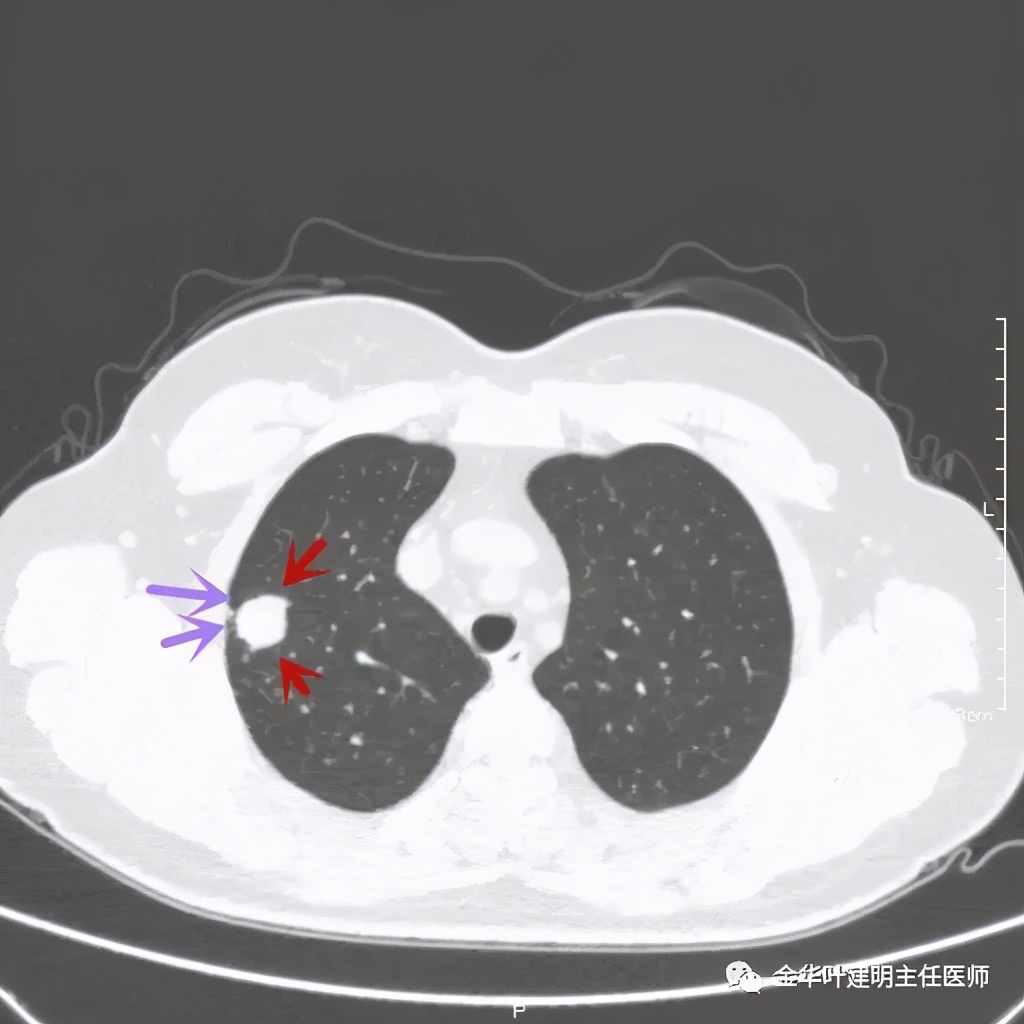

紫色箭头示病灶与胸膜很近,但无牵拉凹陷,绿色箭头示附近有微小其他病灶

上图同样示与胸膜近,但无牵拉